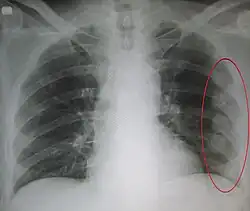

![]() | |

| An X ray showing multiple old fractured ribs of the person's left side as marked by the oval | |